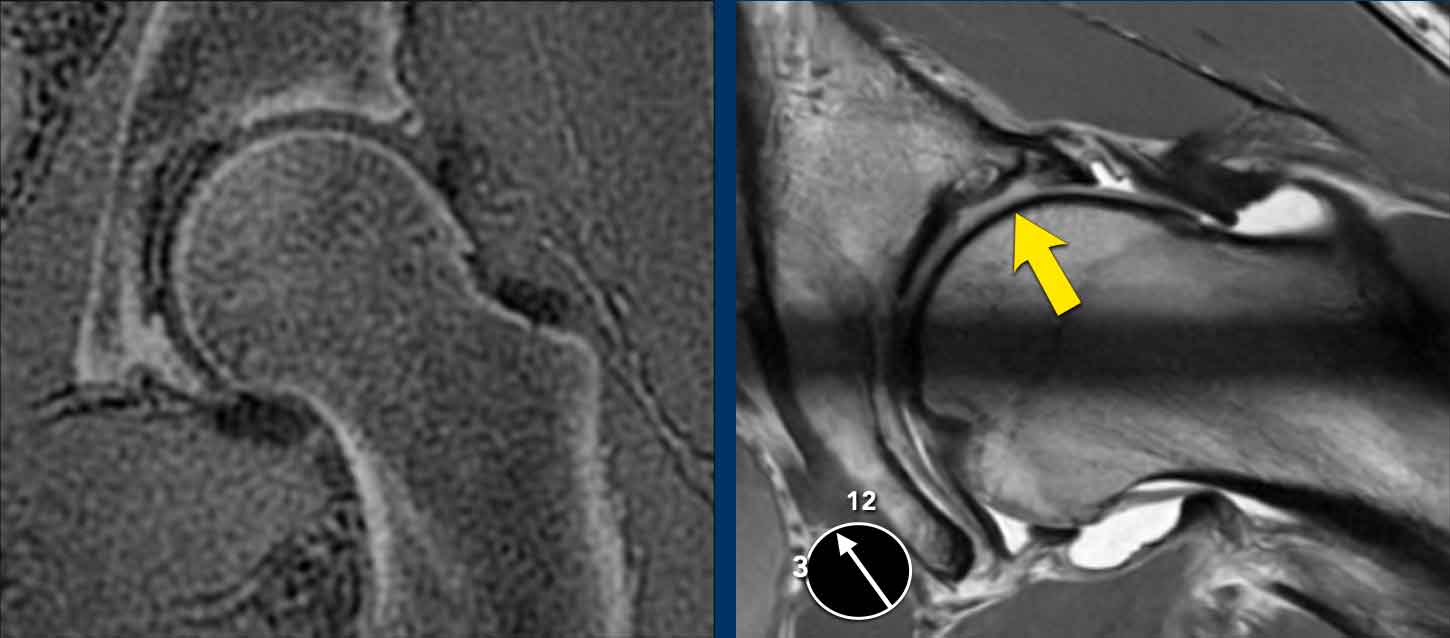

Đây là nam bệnh nhân 27 tuổi, xuất hiện đau sâu vùng bẹn phía trước cách đây bảy năm khi đang ngồi xổm.

Kể từ đó, bệnh nhân đã ngừng chơi bóng đá nhưng vẫn tiếp tục bị đau.

Hình ảnh

Các phim X-quang cho thấy một gờ xương nhô ra ở đầu/cổ xương đùi phù hợp với hình thái cam.

Continue with the MRI…

Hình ảnh bên trái là MRI xương/thời gian echo bằng không (ZTE).

Đây là một kỹ thuật chụp MRI đặc biệt để khảo sát xương.

Các hình ảnh trông khá giống với hình ảnh CT và có thể được thực hiện như một phần của chụp MRI-arthrogram khớp háng.

Hình ảnh cho thấy một gai xương nhỏ (mũi tên đen).

Cuộn qua các hình ảnh của MRI-arthrogram ở phía bên phải.

Có một tổn thương sụn ở phía ổ cối (mũi tên vàng).

Kết luận

Do bệnh nhân này đã có thoái hóa khớp ở mức độ nhẹ, bệnh nhân không phải là đối tượng phù hợp để điều trị nội soi khớp.

Bệnh nhân được điều trị bảo tồn bằng vật lý trị liệu, liệu pháp tập luyện, giáo dục sức khỏe và điều chỉnh hoạt động.